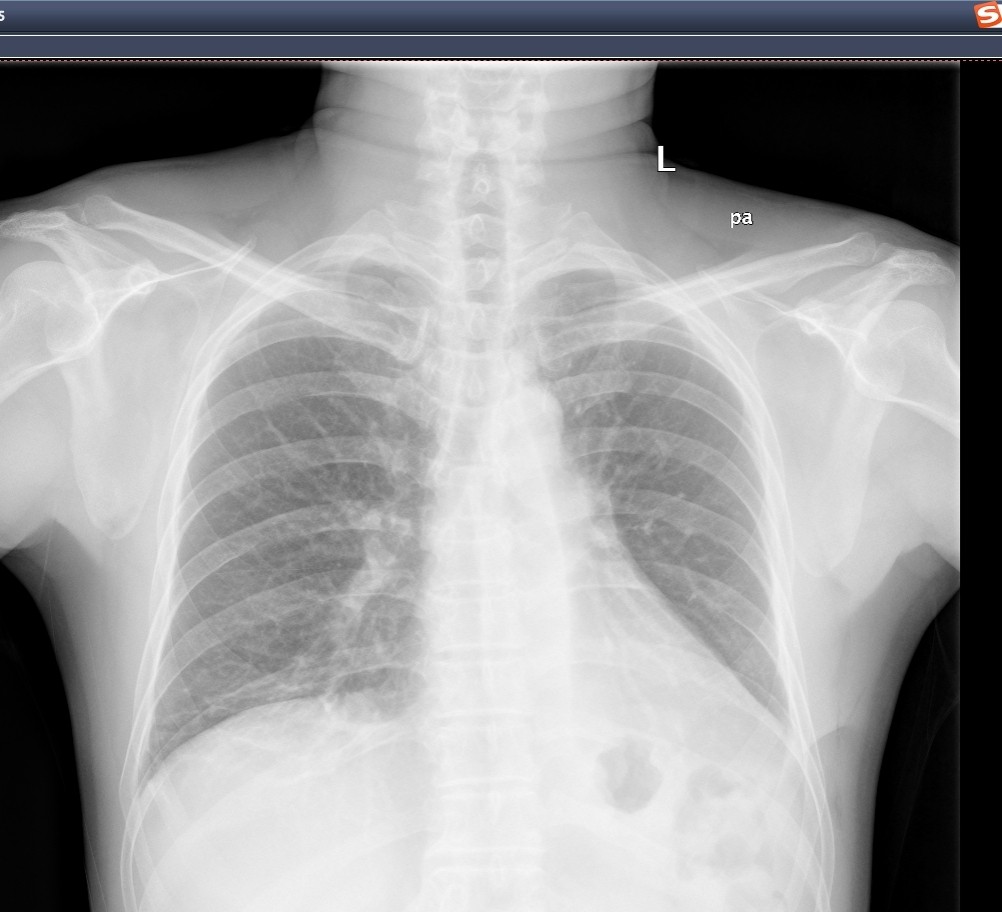

这位患者因胸闷、胸痛7小时入院,胸部CT检查示“右侧气胸,右肺压缩约80%”,既往身体健康状况良好,无传染病或慢性病,无气胸发作史。急诊行右侧胸腔闭式引流排气,术后第2天复查胸片气胸好转,肺膨胀好,见右下肺阴影。完善胸部CT增强发现 右肺下叶外基底段可见一肿块样状实变密度影,边界尚清,边缘不光整,呈分叶状改变,并牵拉邻近胸膜,较大截面约为41mm×30mm,其内支气管截断,平扫CT值约为28Hu,增强扫描病变中央见片状不强化区,边缘呈渐进性强化,CT值分别为52Hu、64Hu、75Hu;病变旁可见一囊腔影,边界欠清,囊壁不规则,周围局部见磨玻璃密度影,较大截面约为37mm×23mm。考虑恶性肿瘤性病变可能性大。

图7:胸部CT肺窗示右肺下叶肿块影伴空洞

图8:增强CT纵隔窗扫描病变中央见片状不强化,边缘呈渐进性强化